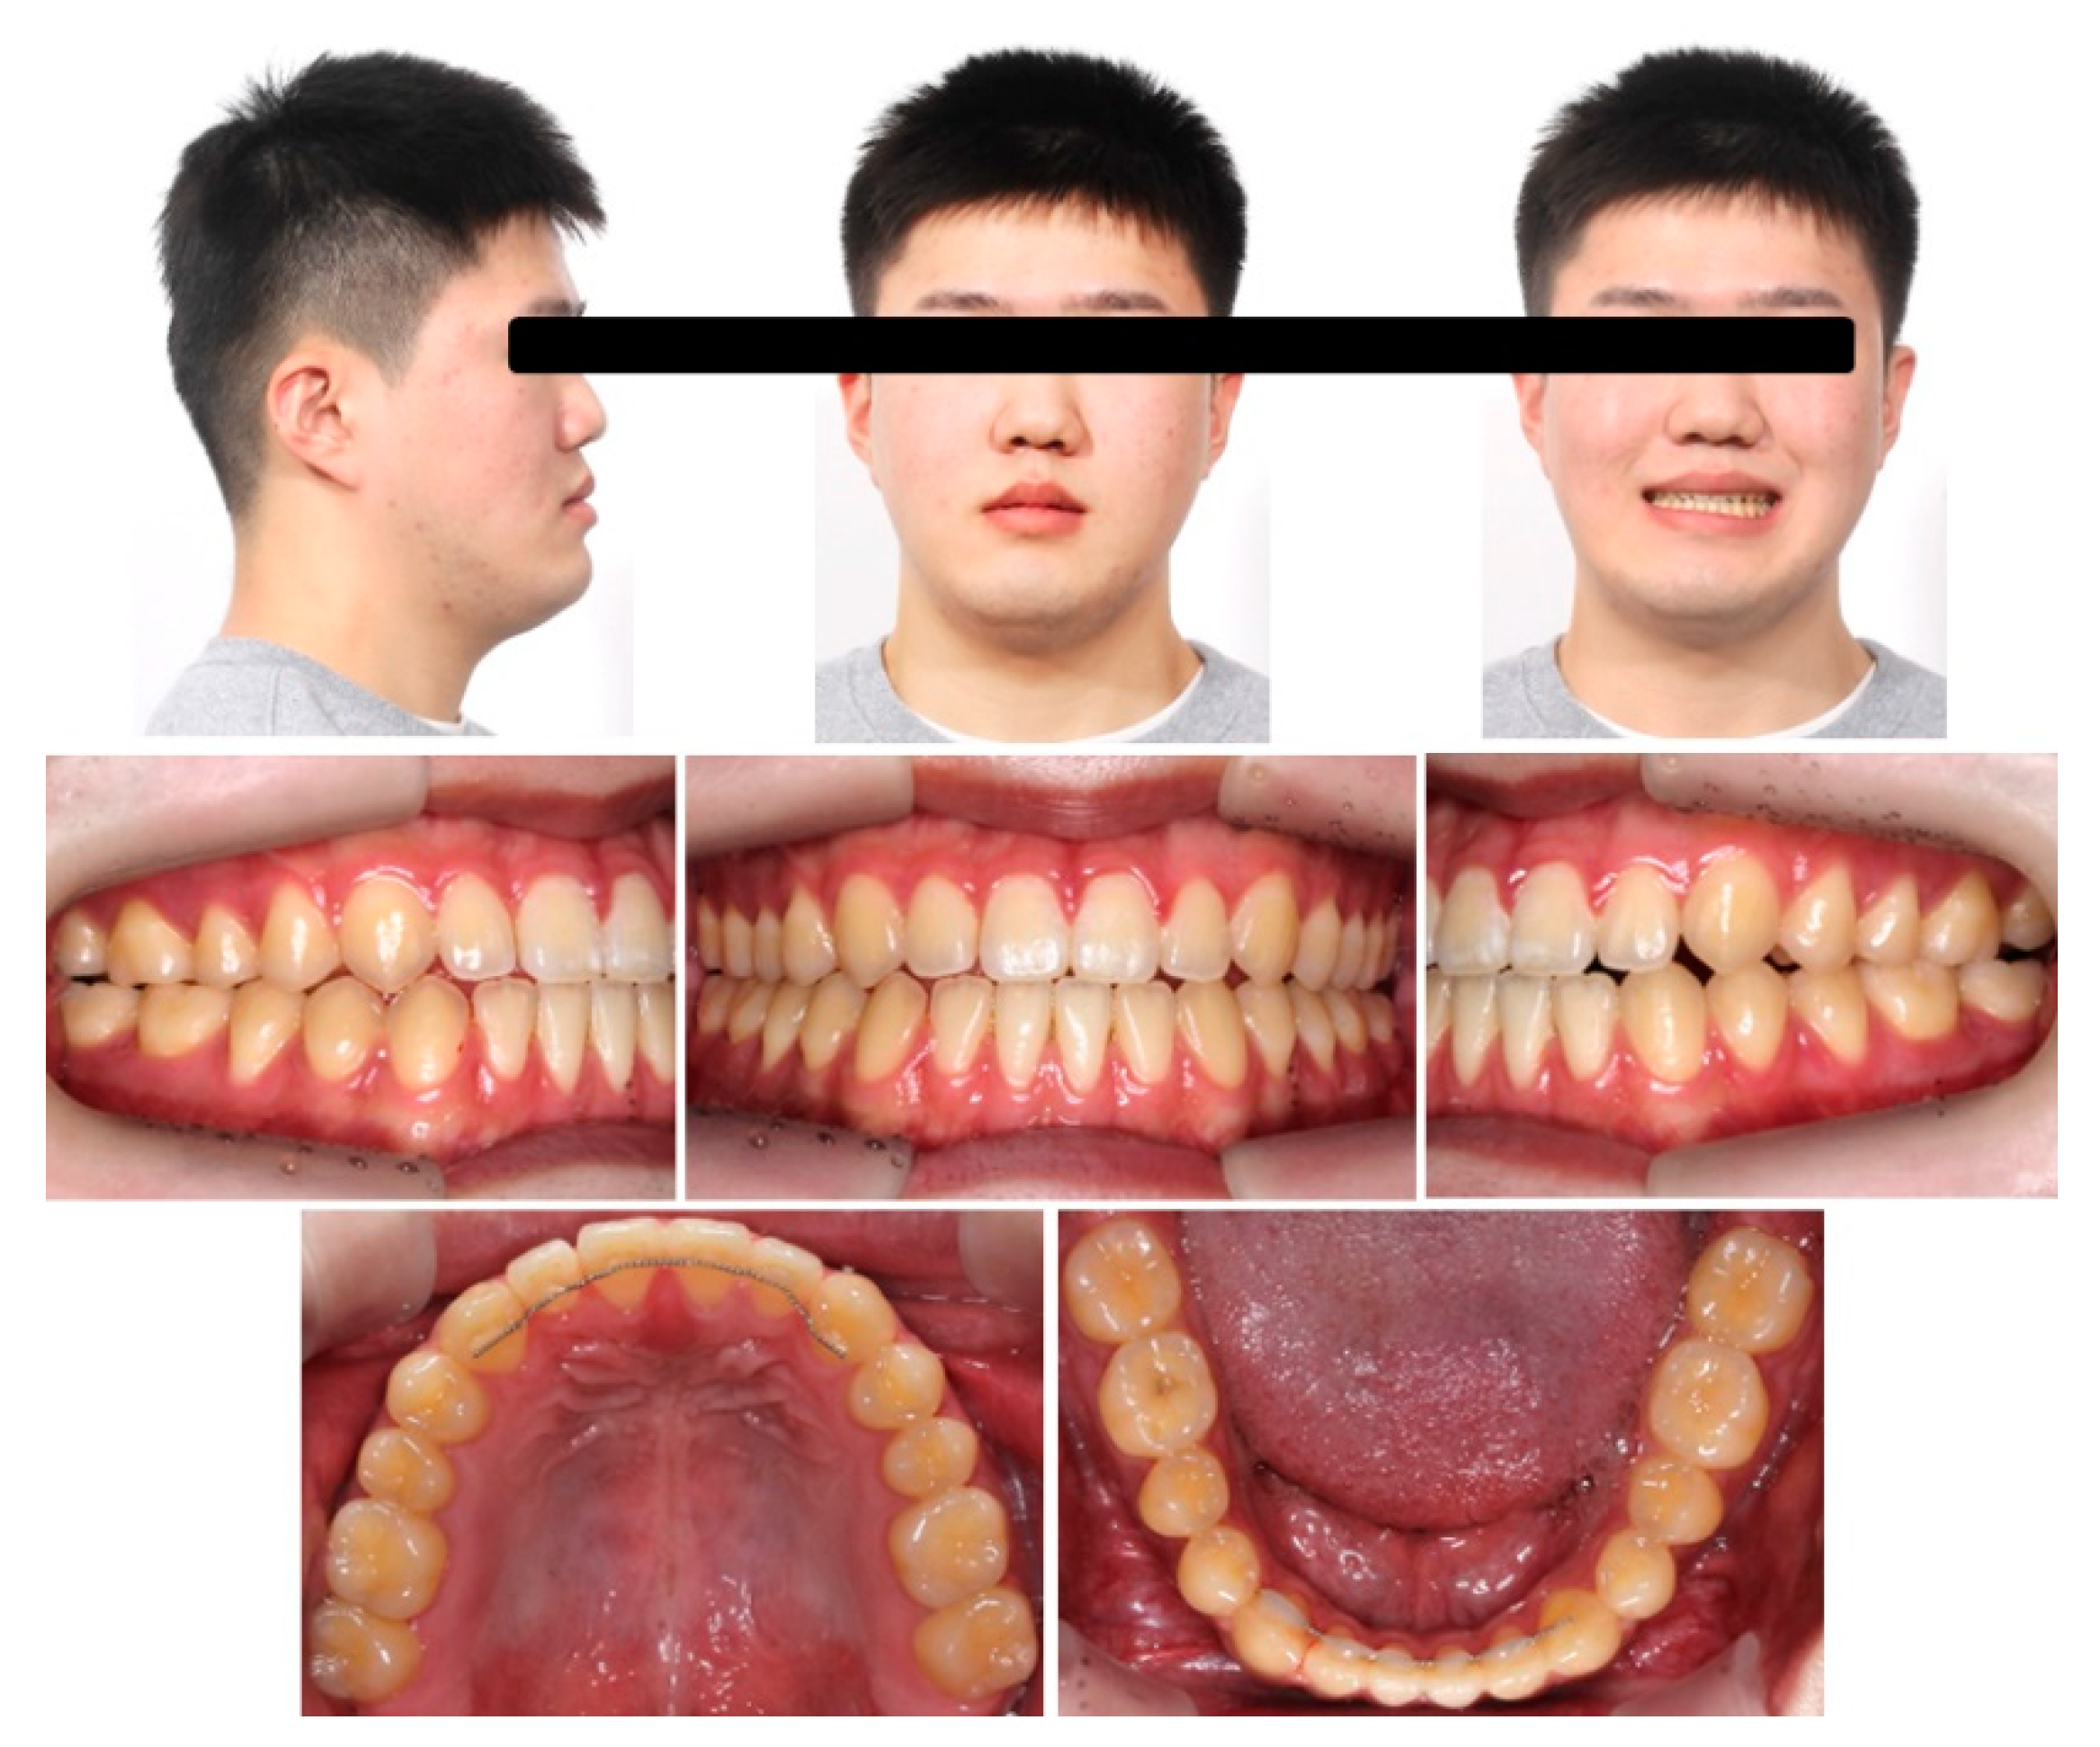

2.5. Treatment Results